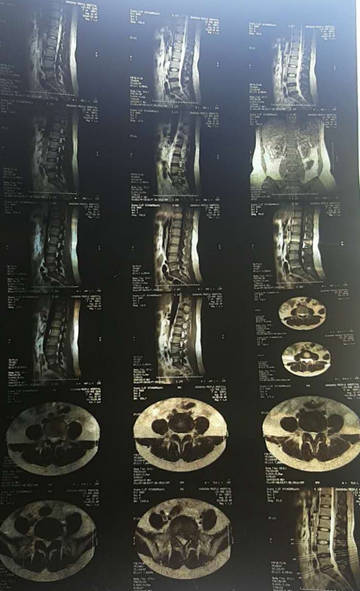

案例一

核磁轴位

核磁矢状位

2007年,刘女士,43岁,L5-S1椎间盘脱出0.8cm,胶州市人民医院外聘专家要求手术。不能行走,夜间痛性,主要表现为腿后侧。